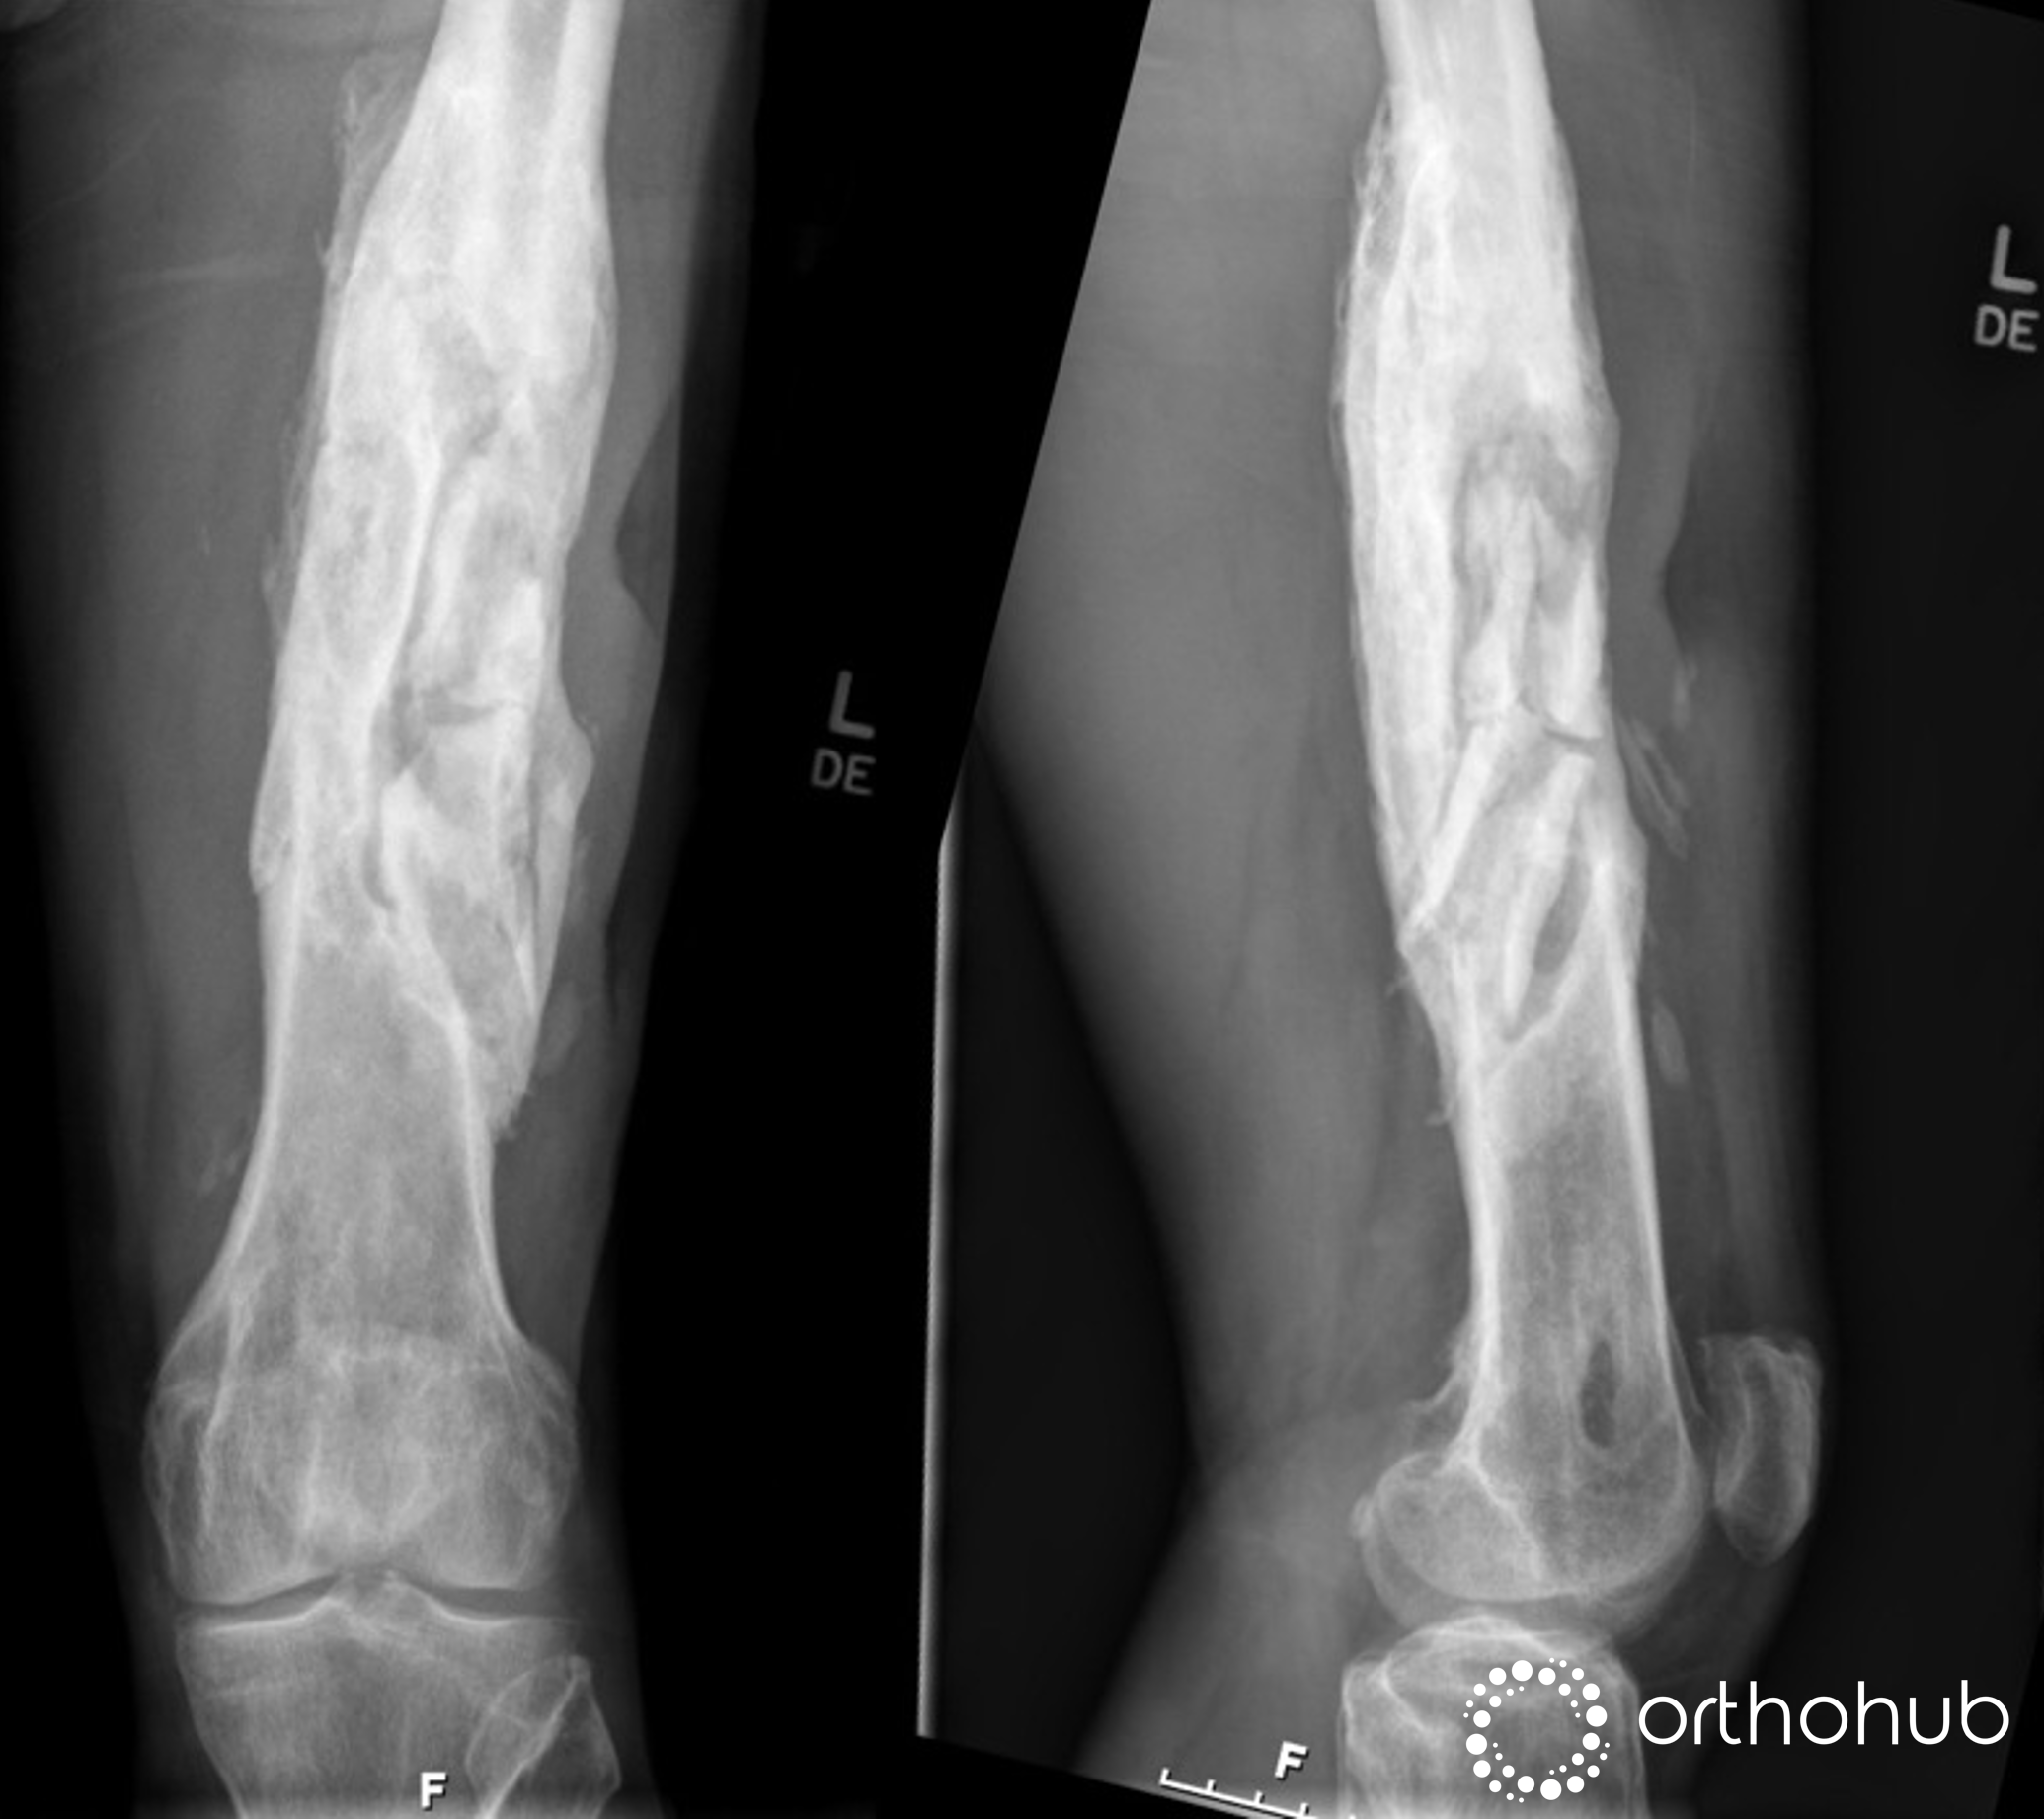

49 year old male who had an open fracture of the left femur in Morocco 20 years previously. Which was treated non-op.

Since then, he's had on/off local drainage and periods of antibiotics

Current situation:

Foul smelling discharge

Dressing changes x5/ day

Requesting amputation (family can't stand the smell)

Non smoker, no co-morbidities, quads adherent limiting knee flexion

Radiographs